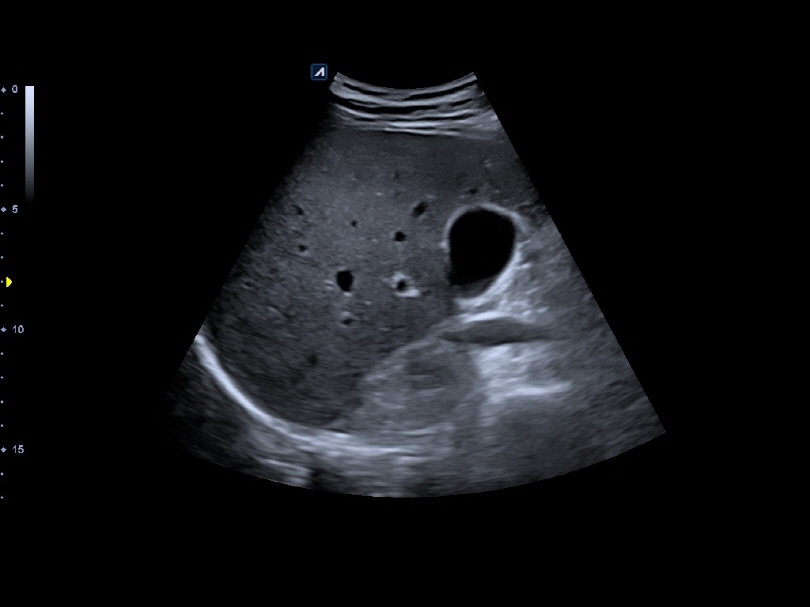

VC1-6T

Volume Convex (1-6MHz)

Application:

Abdomen, OB, GYN, EM